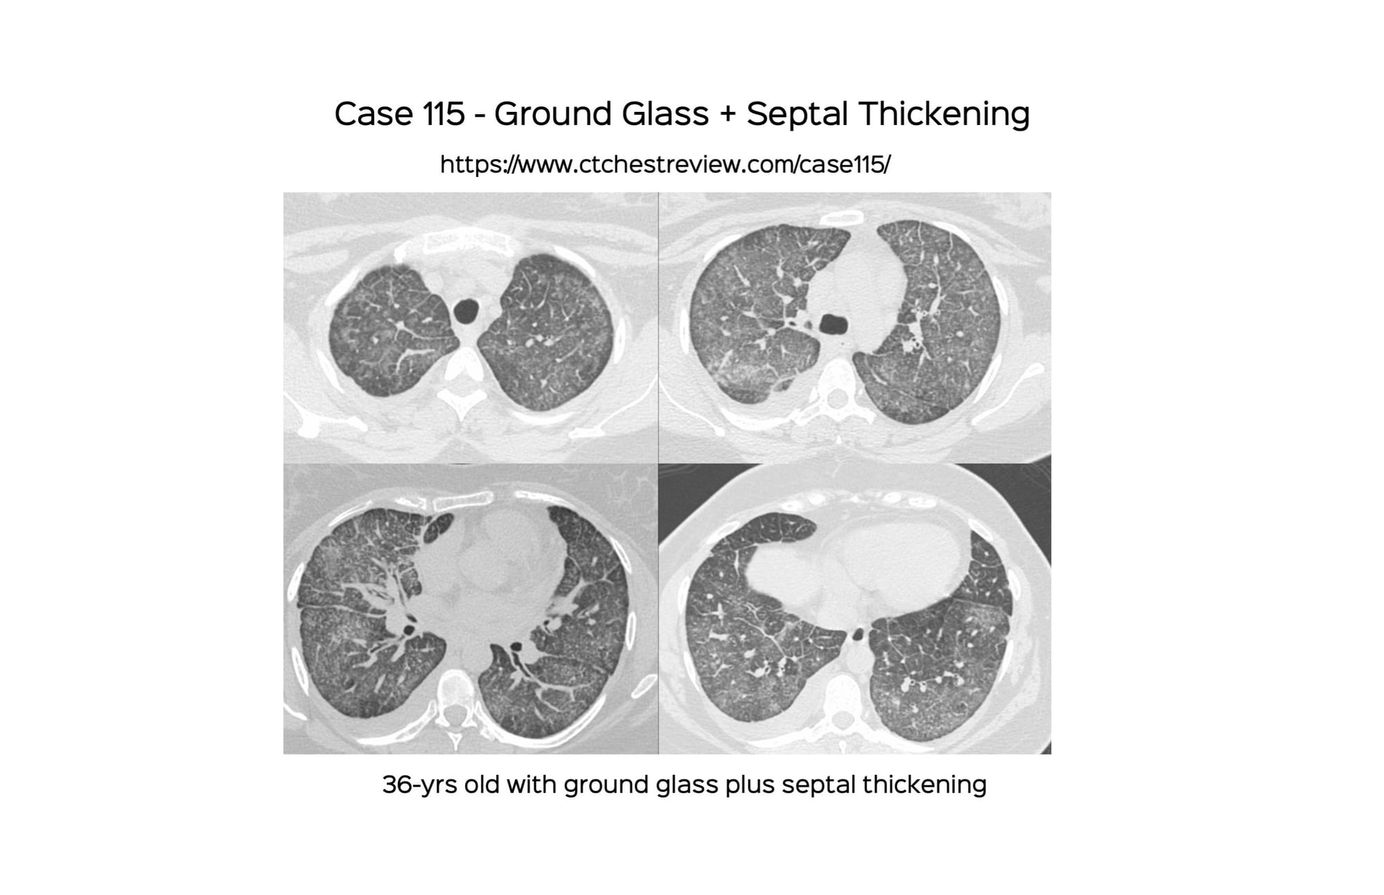

Case 115 - Ground Glass + Septal Thickening Paid Members Public

Ground glass plus septal thickening has a specific set of conditions that can be differentiated based on appearance morphology, presentation (acute/subacute/chronic) and presence of other findings in the chest or elsewhere on whole body scanning